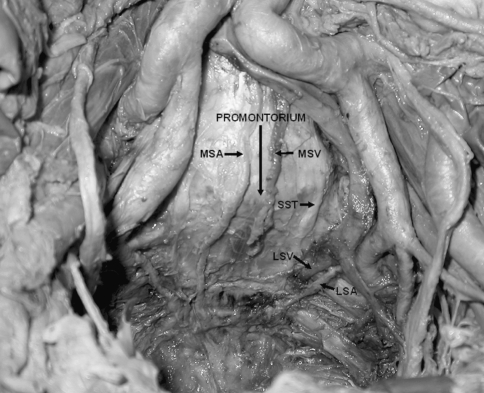

There was no injury to visceral organs. Congenital or anatomic lumbosacral osseos anomalies were not observed. The bifurcation points of both aorta and the inferior vena cava were superiorly located from the promontorium in all cases. The mean distance between promontorium and aortic bifurcation was 62.0 ± 13.1 mm, and the mean distance between promontorium and inferior vena cava bifurcation was 39.4 ± 10.6 mm. Normal topographic relationships of the neurovascular structures are shown in Fig. 1.

Fig. 1.

Normal topographic relationships of the neurovascular structures at the anterior part of the lumbosacral junction (MSA middle sacral artery, MSV middle sacral vein, LSA lateral sacral artery, LSV lateral sacral vein, SST sacral sympathetic trunk)